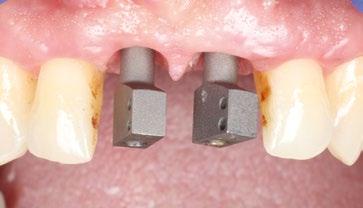

1

Fotos iniciales que muestran claramente el grave compromiso de la arcada superior debido a la enfermedad periodontal. Giovanni Zucchelli Alessandro Zucchelli Pietro Bellone

Tejidos a los 6 meses de curación.

Curación después de la limpieza con provisional reforzado anclado en los elementos residuales 17, 15, 11, 21, 23, 24, 25.